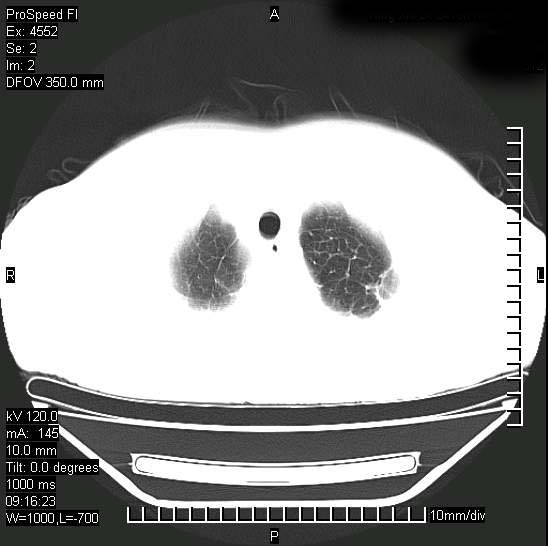

十几年前曾患肺结核,一周前突咳血约100ml,中性粒细胞稍高,诊断两上肺陈旧结核,下肺炎症,给予抗炎治疗,近几日晚上高热,39度,仍咳少量血,4天前ct及今天ct上传。

[face=黑体]8月30日[/face]

支持陈旧性肺结核并两下肺感染,两侧胸腔积液。

考虑1双肺tb灶;右下肺支气管壁增后,建议除外占位 3双侧胸腔积液,

支持  结核ban感染,节段性肺不张,支气管内膜结核可能

继发性结核感染加重。左侧合并有支气管内膜结核。

1)两肺结核并感染。2)不排除左肺上叶中央型肺癌并阻塞性肺炎、肺不张可能;建议行纤支镜检查。3)右肺门及纵隔淋巴结肿大。4)双侧胸腔积液。